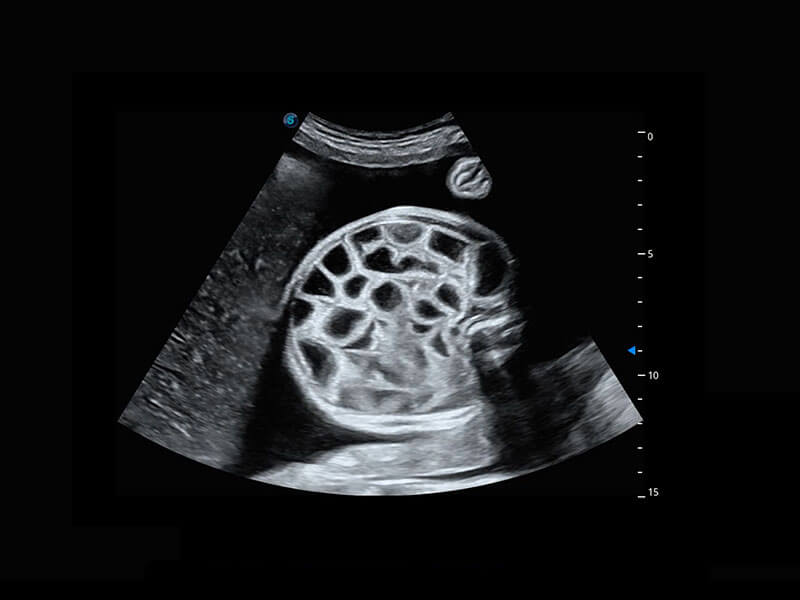

腔内妇科-卵巢

腔内三维-宫内节育器